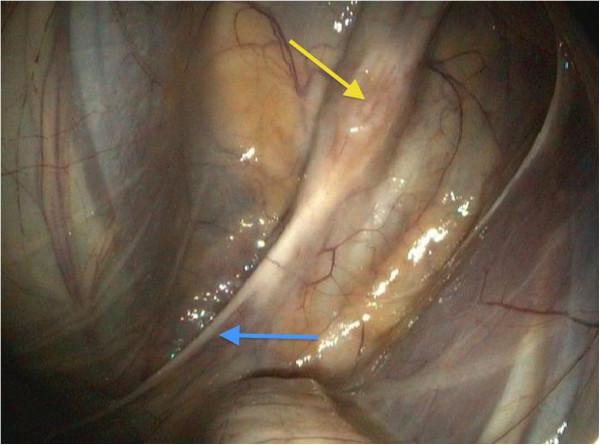

A 20-year-old pony mare was presented to the equine hospital with a ten-day history of dysphagia, regurgitation and coughing. An obstruction of the oesophagus was excluded via endoscopy, but the proximal oesophagus appeared to be distended and circular contractions were missing. A guttural pouch endoscopy revealed a single, black-mottled plaque on the pharyngeal ramus of the vagus nerve in the left guttural pouch, causing a local swelling of this nerve. The pharyngeal ramus seemed to be atrophic distal to the lesion. A biopsy was taken from the lesion and histopathological findings proved the reasonable suspicion of a guttural pouch mycosis with a high degree of purulent-necrotic inflammation and invasion of fungal hyphae. There were no signs of neoplasia, such as melanoma. Daily guttural pouch irrigations with a clotrimazole emulsion (20 g Canesten(®) Gyn(4) solved in 500 ml water), led to a good recovery of the mucosa above the nerve. Periodic endoscopic examination of the left guttural pouch showed that local thickening and distal atrophy of this pharyngeal ramus did not improve, neither did the clinical symptoms. Due to progressive weight loss, acute respiratory distress and aspiration pneumonia, the 20-year-old pony mare unfortunately had to be euthanized three weeks after discharge. This case report emphasizes the enormous importance of a single nerve for the realization of the swallowing process. The one-sided loss of function of the pharyngeal branch of the vagal nerve cannot be compensated neither by the remaining ipsilateral nerves nor by the contralateral normal functioning glossopharyngeal and vagal nerves and thus inevitably leads to severe dysphagia.

一匹 20 岁的母马驹因吞咽困难、反流和咳嗽到马医院就诊,病史已有 10 天。通过内窥镜检查排除了食管阻塞,但近端食管似乎扩张,且圆形收缩缺失。喉囊内窥镜检查显示,左侧喉囊内迷走神经咽支有一个单一的、黑色斑驳斑块,导致该神经局部肿胀。咽支在病变远端似乎萎缩。从病变处取活检,组织病理学检查结果证实了合理怀疑的喉囊真菌病,存在高度化脓性坏死性炎症和真菌菌丝侵犯。没有肿瘤的迹象,如黑色素瘤。每天用克霉唑乳剂(20 克克霉唑阴道片(Canesten(®) Gyn(4))溶于 500 毫升水中)冲洗喉囊,导致神经上方的黏膜恢复良好。定期对左侧喉囊进行内窥镜检查显示,该咽支的局部增厚和远端萎缩没有改善,临床症状也没有改善。由于进行性体重减轻、急性呼吸窘迫和吸入性肺炎,这匹 20 岁的母马驹在出院后三周内不幸被安乐死。本病例报告强调了单一神经对吞咽过程的重要性。单侧迷走神经咽支功能丧失既不能被同侧剩余的神经代偿,也不能被对侧正常功能的舌咽神经和迷走神经代偿,因此不可避免地导致严重的吞咽困难。